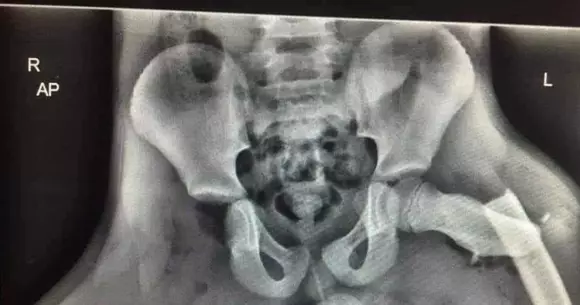

picioare pe bord

Ce poți păți într-un accident dacă îți ții picioarele pe bord